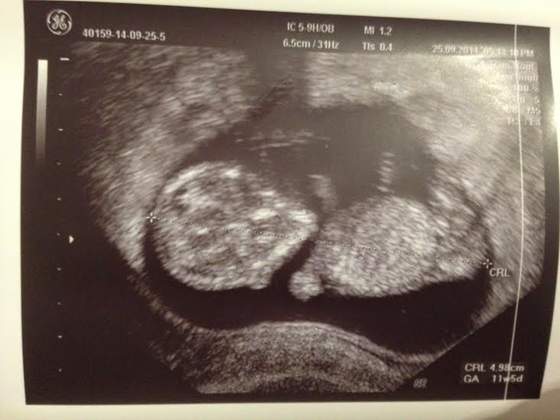

Voila!!! Nasza dzidzia 13tc, nozki skrzyżowane podkurczone, udało sie tylko ciut podejrzec i ..niewiele było widac lol pani położna była skłonna bardziej na dziewczynkę i faktycznie nasz pierworodny na tym etapie miał juz wszystko na swoim miejscu :D ImageUploadedByForum BabyBoom1411860269.264584.jpg

Załączniki

• ImageUploadedByForum BabyBoom1411860269.264584.jpg

ImageUploadedByForum BabyBoom1411860269.264584.jpg

33,1 KB · Wyświetleń: 151